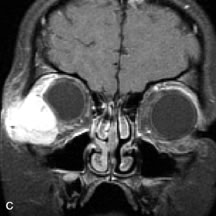

Cystic Lesions

Dermoid cysts appear as rounded, well-defined lesions typically contiguous with an orbital bony suture. The high-intensity signal on T1-weighted images is attributed to the sebaceous-produced lipid contents (Fig. 18).31,50 Mucoceles may demonstrate a hypointense or hyperintense signal on MR images, depending on the concentration of proteinaceous or inflammatory fluid components. The integrity of the bony walls of the expanded sinus cavities cannot be assessed on MR as well as by CT.37,50,55,56 A high-signal intensity on Tl- and T2-weighted images is characteristic of orbital chronic hematic cysts because of the blood-breakdown products within the cysts.57

Fig. 18. A. T1-weighted, (B) T2-weighted fat-suppressed, and (C) T1-weighted fat-suppressed MR scans demonstrate a small dermoid cyst arising near the palpebral portion of the lacrinal gland (arrows). The lesion is similar in signal intensity to fat on the T1-weighted scan (A) consistent with a high adipose tissue content. The lesion shows fat-suppression and low signal intensity on the two fat-suppressed sequences (B and C) confirming its high lipid content.